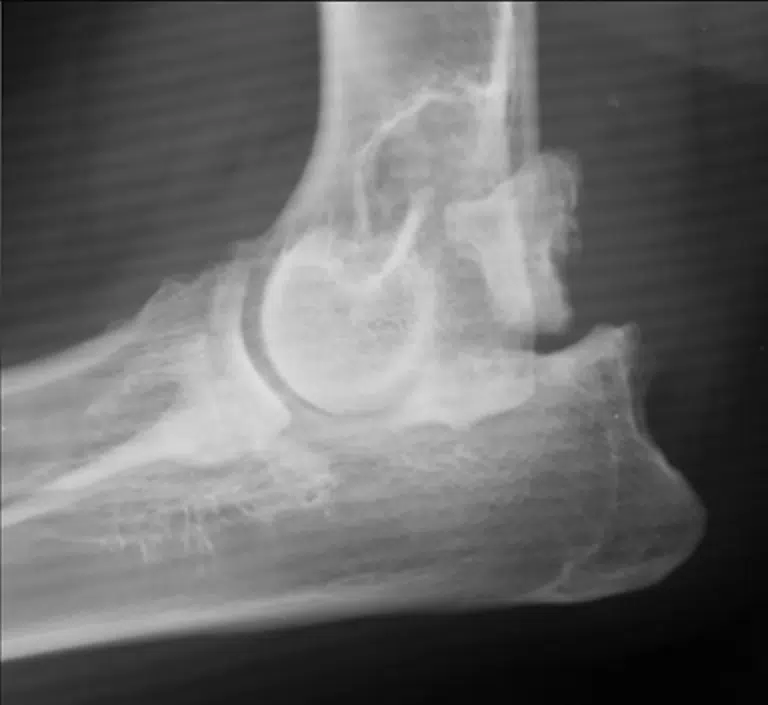

OCD